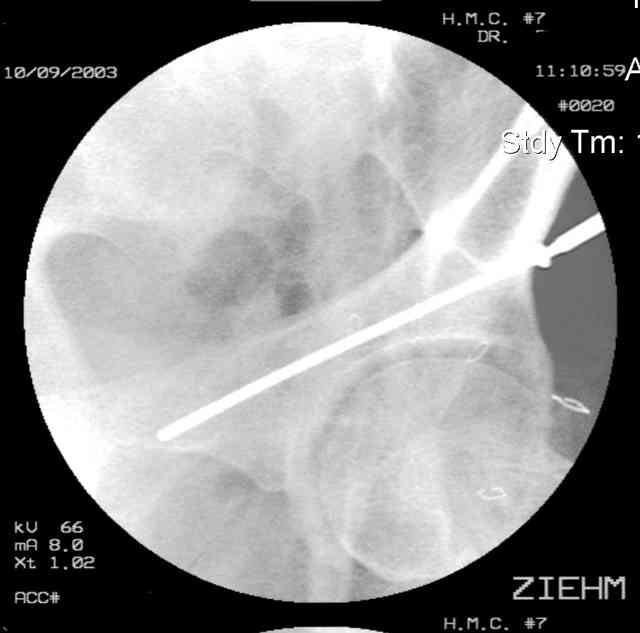

Prone

Here's a pic from the foot of the bed and you can see the clamp in the wound and the knee is extended so he must've had a tight rectus. The C-arm is rolled back to an obturator oblique image to reveal the anterior column...we put a slight outlet tilt to combine the images and give a better view of the anterior column...we can see the posterior column limb reduction in the wound, we can palpate the quadrilateral surface limb, and the image demonstrates the anterior column portion...you can adjust the tilt and rotation to image tangentially to the fracture plane if you'd like. We've inserted a 2mm K wire to site the starting point and aim/orientation for the drill and screw

Prone Imaging

same image, just another look.

Prone Inlet

OK, now we're inserting the drill percutaneosuy using a sleeve. This fluoro shot is not for this patient (notice no clamp) but I was too lazy to go searching the PACS for one with the clamp on, so pretend...I'll save the next ones and send along...the imaging is the same and the clamp doesn't obstruct imaging other than very rarely...you can always tilt the C-arm a bit to clear it if the clamp obstructs the exact spot that you'd like to see. We'll assume that everyone knows the safe zone for a medullary ramus screw. Use a calibrated drill and sleeve of known length to simplify your life...or use Alex's fancy cannulated screws...I like 3.5mm screws because the oscillating 2.5mm drill bounces and remains intraosseus when it oscillates and contacts endosteal cortical ramus... so will the screw, and like a long bent screw IF the fracture is clamped... if unclamped, when the screw contacts the endosteum, it pushes the reduction apart instead of bouncing. The big 7mm cannulated screws fit few patients and extrude...we very rarely use them any more...you'll see an old one later.

Prone Obturator-Outlet

Screw insertion using the obturator-outlet combination image.